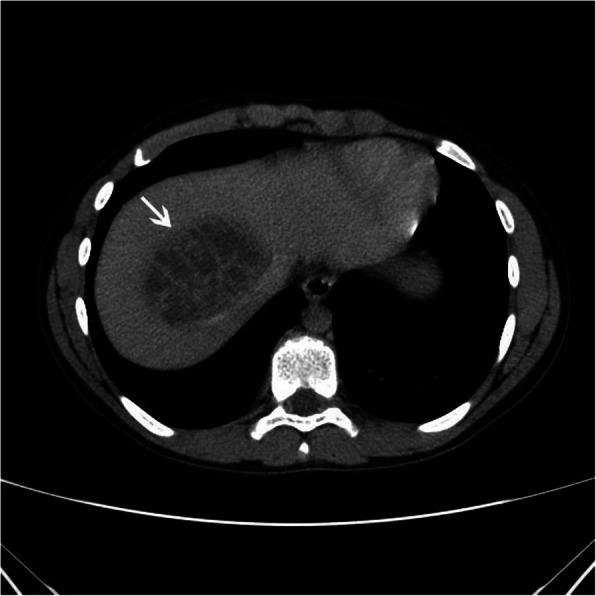

A 13-year-old Caucasian boy presented to the regional hospital with a two-day history of abdominal pain, fever up to 40 °C, and polyuria. Three weeks before the symptoms appeared, the boy had fallen off his bicycle and sustained a handlebar injury to his upper abdomen. However, he was completely asymptomatic in the meantime and, when asked about the possibility of a recent abdominal trauma, the child and his mother at first denied any such event. Apart from that, his general past medical history was unremarkable. Physical examination on admission revealed a soft, non-tender, and non-distended abdomen, without masses. The liver and spleen were not palpable below the costal margins. The laboratory tests showed significantly elevated inflammatory parameters (C-reactive protein (CRP) of 154.68 mg/L and erythrocyte sedimentation rate of 53 mm/h), leukocytosis (his white blood cell count was 13.81 × 109/L), and mildly elevated levels of aminotransferases (alanine aminotransferase (ALT) and aspartate aminotransferase (AST) levels were 77 IU/L and 52 IU/L, respectively). The urinalysis did not detect the presence of nitrites and white blood cells, and his urine culture was negative. Abdominal ultrasound revealed a unifocal, predominantly hypoechoic lesion in the right hepatic lobe, with irregular internal echoes. Contrast-enhanced portal phase computed tomography (CT) scan showed a single, well-defined, low-attenuation liver lesion, located in the segment VIII, measuring 65x56x41mm (LLxAPxCC) (Fig. 1). The lesion was multiloculated, with contrast-enhanced internal septa, which represents a “cluster sign” of PLA. Right and middle hepatic veins were compressed and slightly dislocated by lesion, but patent. Empiric antibiotic therapy was initiated with ceftriaxone, and subsequently, amoxicillin/clavulanate was added. Enzyme-linked immunosorbent assay (ELISA) for the determination of anti-Echinococcus IgG antibodies was negative. On the fourth day after admission, the boy’s overall condition significantly improved, and he was afebrile for the rest of his hospital stay in the regional hospital.

Fig. 1.

Axial contrast-enhanced portal phase CT image shows a single, low-attenuation, multilocular lesion in the segment VIII of the liver